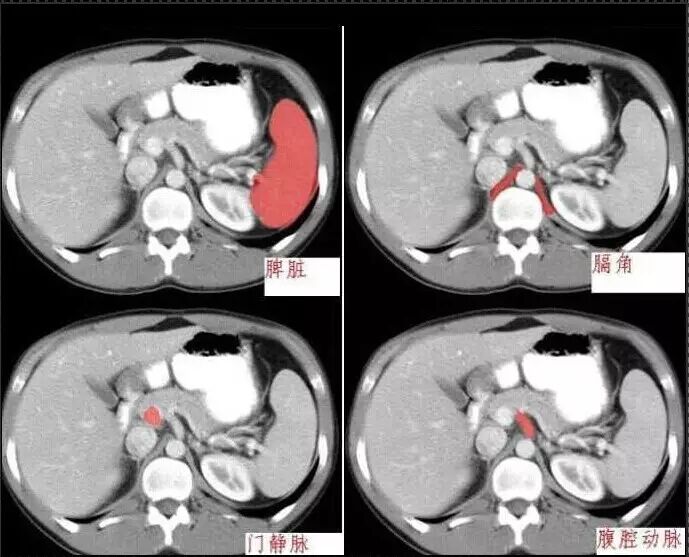

十分钟学会腹部CT解剖(多图)